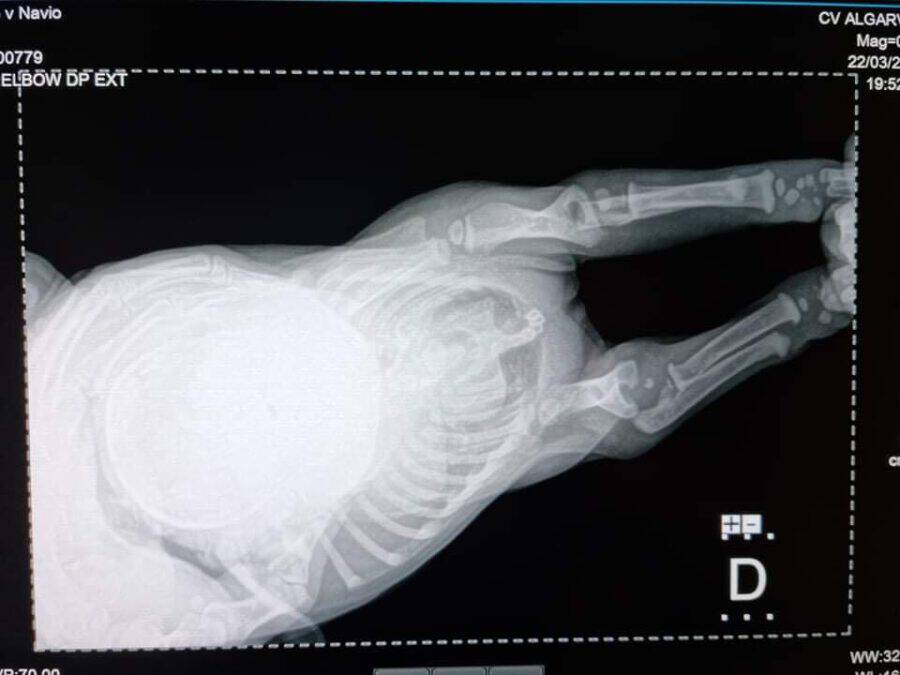

Der kleine Mickey war erst ca. 4 Wochen alt und musste in seinem kurzen Leben schon viel aushalten. Seine Rute wurde abgeschnitten und sein Vorderbein war ausgerenkt. Wir waren deshalb direkt bei unserem Knochenspezialisten, der versucht hat, das kleine Beinchen wieder einzurenken. Leider hat dies nicht geklappt und Mickey bekommt aktuell Physiotherapie.

Eine erneute Untersuchung und Röntgen im Juni 2022 haben gezeigt, dass seine Knochen im Vorderbein so verdreht sind, dass eine Operation nicht erfolgversprechend ist. Aktuell kann Mickey mit seinem Handicap schmerzfrei und mit wenigen Einschränkungen gut leben. Er bekommt zusätzliche Vitamine aber es ist möglich, dass sich sein Ellbogengelenk mit zunehmendem Gewicht entzündet und eine Amputation des Beines notwendig wird.